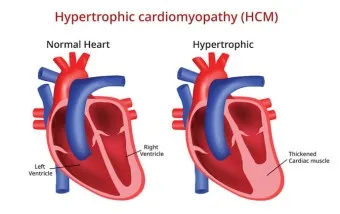

1. 심장 관련 원인

- 부정맥: 정상 심박수 범위 60-100회/분 이탈

- 심장 판막 이상: 증상 발현 시 심박수 변동 20% 이상